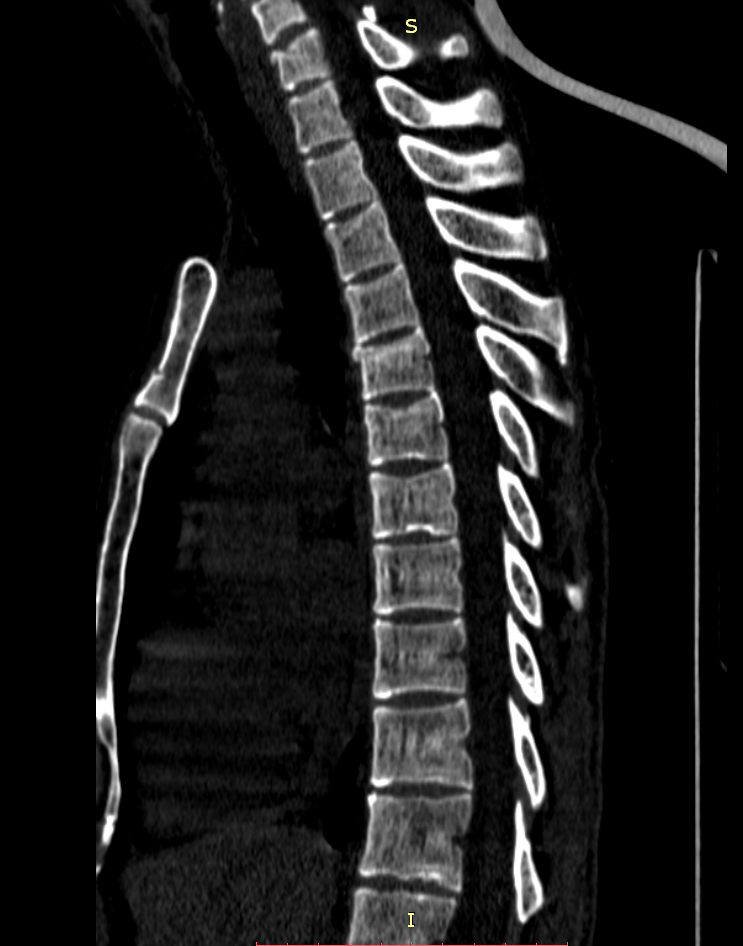

Здравствуйте! Меня сбил автомобиль. Бригада скорой помощи доставила меня в стационар с диагнозом - сотрясение мозга, ушиб грудного отдела позвоночника, компрессионный перелом грудного отдела позвоночника. При поступлении в стационар мне было сделано несколько рентгеновских снимков и поставлен диагноз - компрессионный перелом 4 грудного позвонка. Из-за "мутных" рентгеновских снимков через 9 дней мне сделали КТ и диагноз сняли на основании этого заключения.Судебная медицина - Прикрепленное изображение Мне сказали что перелом шейного позвонка у меня старый и поменяли диагноз - ушиб верхне-грудного отдела позвоночника, болевой синдром. По запросу я получила копию записи КТ. Всю запись КТ выложить не могу, т.к. не могу убрать фамилию. Выкладываю некоторые снимки: Судебная медицина - Прикрепленное изображение Судебная медицина - Прикрепленное изображение Судебная медицина - Прикрепленное изображение Судебная медицина - Прикрепленное изображение Судебная медицина - Прикрепленное изображение Судебная медицина - Прикрепленное изображение Судебная медицина - Прикрепленное изображение Действительно ли по этим снимкам можно сказать, что перелом шейного позвонка "старый"? Правильно ли описание КТ? Я не эксперт, но по-моему 5 грудной позвонок тоже поврежден. Можно ли оспорить заключение врача делавшего КТ? Если можно, то как это сделать? Ведь речь идет об установлении причинно-следственной связи между ДТП и травмой, а до ДТП у меня никаких травм позвоночника не было. Может рентгеновские снимки тоже о чем то скажут.Судебная медицина - Прикрепленное изображениеСудебная медицина - Прикрепленное изображениеСудебная медицина - Прикрепленное изображение

Для этого надо исследовать все сканы. Желательно - с 3D-реформацией изображения. С внимательным анализом костной структуры на уровне дефекта (есть ли признаки отека костной ткани в его зоне, наличие реакции мягких тканей, состояние краев фрагментов и т.д.). Получите все сканы КТ на диске или на флешке (они должны храниться в архиве КТ). И проконсультируйте их у высококвалифицированного специалиста по КТ и/или в любом крупном Бюро судебно-медицинской экспертизе, в штате которого есть эксперт-рентгенолог. Возможно, понадобится сделать контрольное КТ исследование с целью обнаружения динамики выявленных изменений (впрочем, вопрос об этом будет решен после ознакомления рентгенолога с КТ, т.к., возможно, доп.исследование не будет необходимо или же более целесообразным окажется иной вариант лучевой диагностики). По результатам консультации станет понятно, есть ли реальные основания для заявления мотивированного ходатайства о назначении дополнительной или повторной экспертизы (как это сделать - подскажет Ваш адвокат).